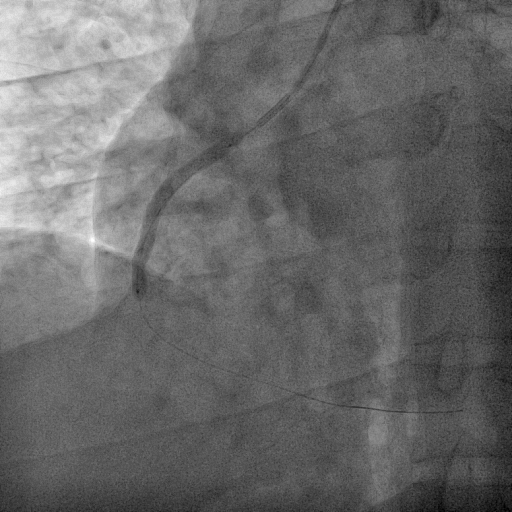

We decided to proceed with the primary percutaneous coronary angioplasty via right radial access by using the 5F JR 3.5 guiding catheter . We used Run through NS floppy wire for crossing culprit lesion to distal RCA but TIMI flow 0. We used micross 1.0 balloon for just cross the lesion and tracking balloon over the lesion . Then distal segment properly seen. Pre dilatation not done due to acute lesion and high chance of thrombus dislodgement and distal embolization . Direct stent 3.50 x 42 mm was implanted in proximal RCA to Mid RCA at 14 atmosphere pressure. Stent was well apposed and final result angiography was excellent and TIMI III flow without residual lesion and no distal embolization. the procedure done without any complications. Total Inj. heparin 10000 unit given and ACT was 298 sec.

SHAHIDUL ISLAM_(S8_F1-57).avi

SHAHIDUL ISLAM_(S12_F1-23).avi

SHAHIDUL ISLAM_(S14_F1-46).avi